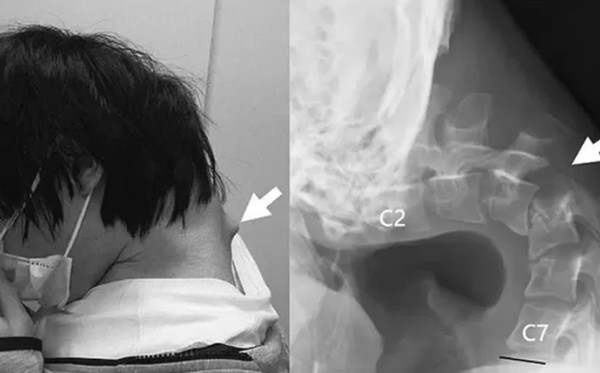

Thanh niên này chơi game rất nhiều trên điện thoại, thế rồi dần dần, ở gáy sưng to lên và anh ấy không thể ngẩng được đầu lên nữa. Chưa hết, anh này còn rất đau cổ và khó nuốt thức ăn. Đến lúc đó anh mới tới gặp bác sĩ.

| Tình trạng cổ của bệnh nhân khi gặp bác sĩ. Ảnh: ScienceDirect. |

Việc chụp chiếu đã cho thấy các đốt sống cổ của anh bị biến dạng và không còn ở đúng vị trí. Những mô sẹo đã hình thành ở phần trên của cột sống.

Ban đầu, các bác sĩ cố gắng điều trị cho anh này bằng nẹp cổ nhưng không được, vì vậy, họ đành thực hiện nhiều ca phẫu thuật, đưa các vít và thanh kim loại vào để điều chỉnh tư thế cho bệnh nhân.

6 tháng sau các ca phẫu thuật, bệnh nhân đã có thể ngẩng đầu và giữ tư thế đúng.